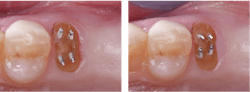

- When one-half or more of the coronal tooth structure is gone, increase the remaining tooth strength by building it up with strongly secured composite resin to allow for the prep anatomy described above.

- Use retentive pins when necessary for retention of the buildup material. Place each pin at least 15 degrees from the long axis of the tooth (examples of titanium pins: Stabilok Dentin Pins or Filpin Pins (figure 3).